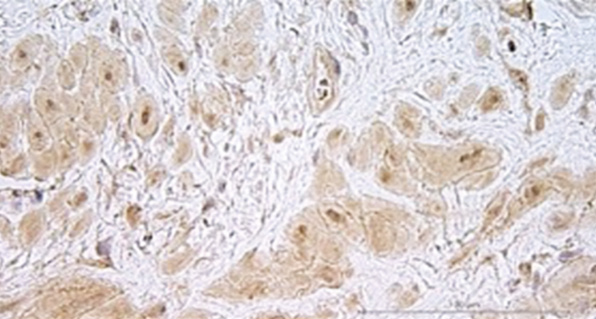

По данным гистологического исследования диагноз «плацентарная адгезивно-инвазивная патология» подтвержден в 100 % случаев (n = 5). При этом микроскопически среди гипертрофированных мышечных волокон визуализированы ворсины хориона с отеком стромы, гиперваскуляризацией и неравномерным полнокровием, а также базальная пластина с эктазией просветов и неравномерно полнокровными сосудами, очаговым некрозом, расслаивающими кровоизлияниями, избыточным количеством фибриноида (рис. 2, а, b).

Рис. 2. Микрофотографии биоптатов миометрия из маточно-плацентарной области: a — ворсина хориона в биоптате миометрия при плацентарной адгезивно-инвазивной патологии (PAS 3a–c); b — децидуальная оболочка в биоптате миометрия при плацентарной адгезивно-инвазивной патологии (PAS 3a–c); c — фрагмент миометрия группы сравнения с полнокровием капиллярного русла из области прикрепления плаценты; d — фрагмент миометрия группы сравнения с участком децидуальной ткани из области прикрепления плаценты; e, f — фрагмент миометрия контрольной группы с участком децидуальной ткани. Окраска гематоксилином и эозином, увеличение ×200

При микроскопическом исследовании гистологических препаратов группы сравнения без клинических признаков врастания плаценты визуализированы фрагменты гладкомышечной ткани с пучками коллагеновых волокон, крупноочаговыми кровоизлияниями. Однако в ткани рубца обнаружены клетки трофобласта, расположенные линейно и мелкоочаговыми скоплениями (рис. 2, c). В биоптатах данной группы найдены фрагменты децидуальной ткани с мелкоочаговой периваскулярной мононуклеарной инфильтрацией, не обнаруженные в группе пациенток с рубцом на матке и ПАИП (рис. 2, d).

Микроскопическая картина биоптатов миометрия группы 3 существенно не отличалась от картины биоптатов группы 2 и представлена гипертрофированными миоцитами с тонкими прослойками соединительной ткани. В отличие от микроскопической картины основной группы, в образцах миометрия контрольной группы визуализированы участки децидуальной ткани с мелкоочаговой мононуклеарной инфильтрацией и неравномерным полнокровием сосудов (рис. 2, е, f).